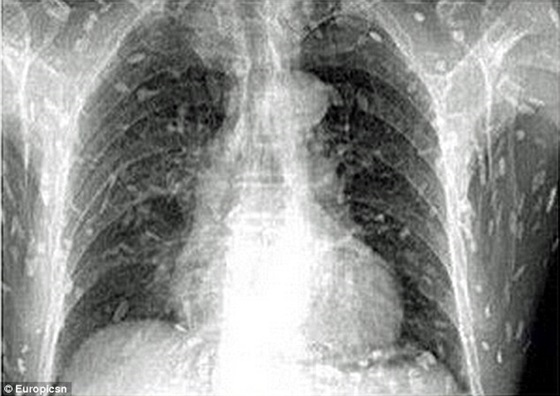

وكان الرجل ذهب إلى الطبيب يشكو من ألم في المعدة وحكة في الجلد، وكشفت الأشعة أن جسمه بالكامل أصيب بعدوى الدودة الشريطية .

وقال الدكتور يين، من مستشفى جوانجتشو، إن تناول الطعام غير المطبوخ الملوث ببيض الدودة الشريطية يمكن أن تسبب داء الكيسات المذنبة في نهاية المطاف، عندما تدخل الديدان البالغة مجرى الدم لشخص ما، وهذا النوع من العدوى يسبب الوفاة فوراً في حالة الوصول إلى الدماغ.